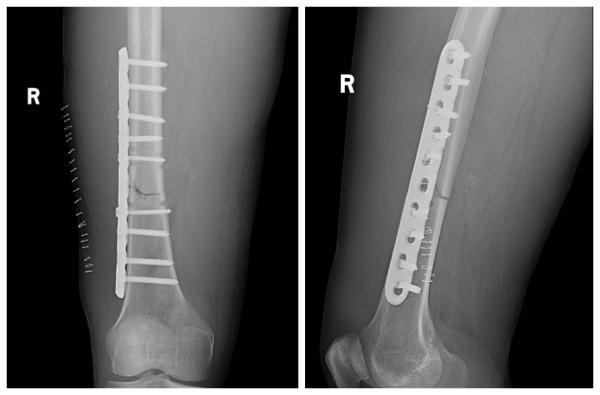

近日,57歲的秦先生因外傷傷及胸部、右大腿,劇烈疼痛,不能站立行走,呼叫120送至濟南南郊醫(yī)院急診中心救治。經診斷,秦先生為右股骨干骨折、肋骨骨折。

結合術前檢查及綜合評估,創(chuàng)傷組組長姜潼宇、主治醫(yī)生薛澤剛及團隊,針對右股骨干骨折采用右側股骨干骨折切開復位內固定術的微創(chuàng)手術。在右側股骨骨折端取8cm手術切口,放置長達15cm鋼板,骨折端切開插入鋼板,避免的開大刀,微創(chuàng)小切口,減少損傷。通過該微創(chuàng)手術,大大縮短了骨折愈合期,提高了患者的生活質量。目前,秦先生的右下肢已經能夠進行功能康復訓練。